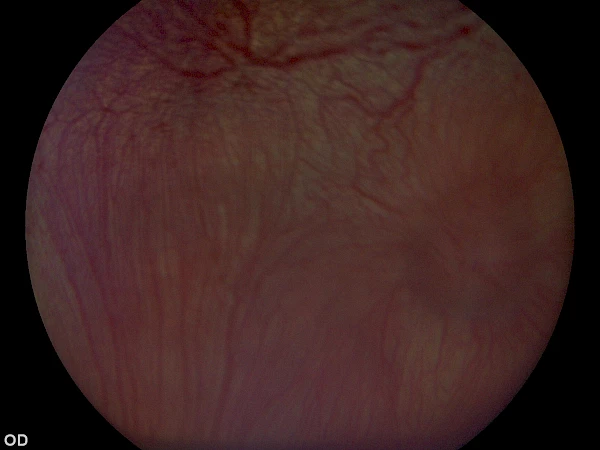

Beispiel einer erfolgreichen Netzhautoperation inkl. Endolaser, von Chris Dixon Beispiel einer erfolgreichen Netzhautoperation inkl. Endolaser, von Chris Dixon

Vitreoretinale Chirurgie (Netzhautoperation, Anlegen der Netzhaut eines Hundes), v. Chris Dixon Vitreoretinale Chirurgie (Netzhautoperation, Anlegen der Netzhaut eines Hundes), v. Chris Dixon